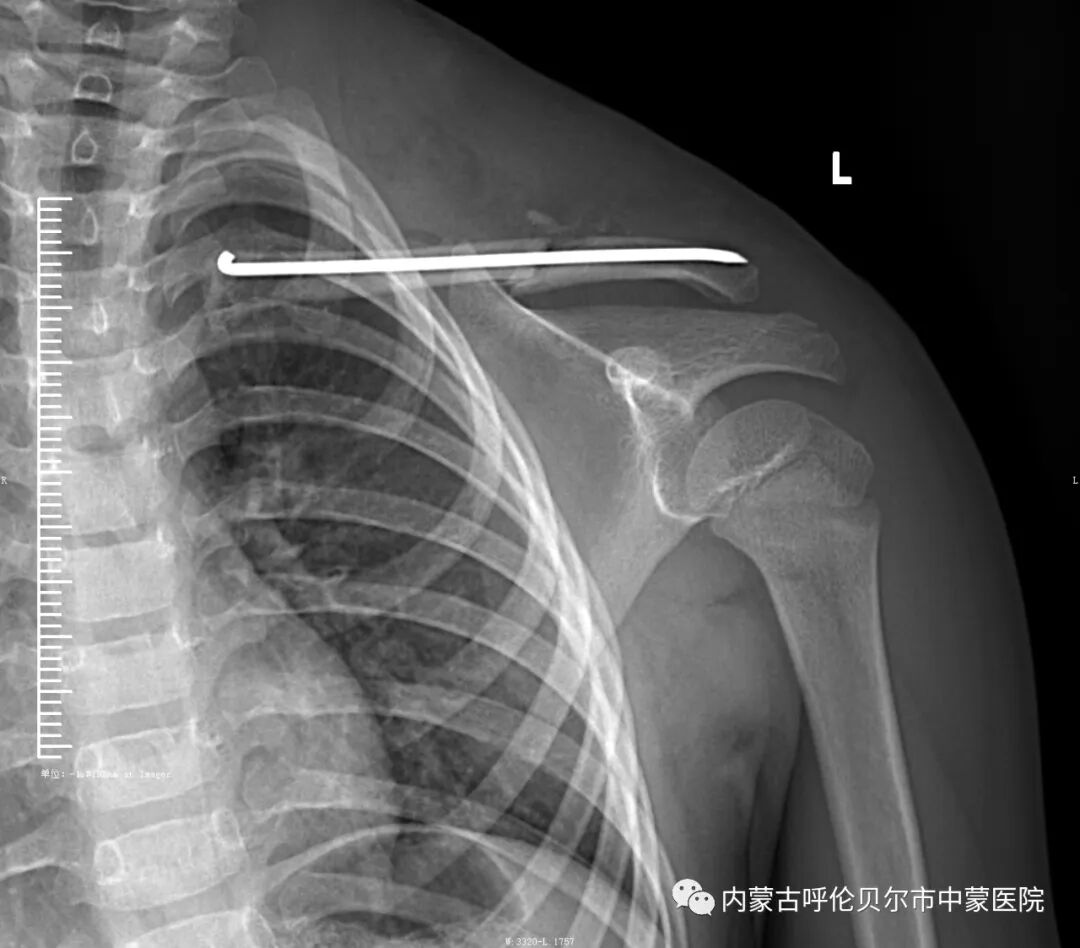

儿童1,来我院就诊前三天在家玩耍时摔伤。当时左侧肩部着地致左侧肩部疼痛、肿胀、活动受限,在家人陪同下于当地诊所捏骨治疗,但症状未见好转,遂来我院就诊,以"左侧锁骨骨折"收住院。

上述两名儿童入院后,我院骨伤科医疗团队制定和完善诊疗方案,充分进行讨论后,决定行微创手术。该项手术可以做到“零切开”,无明显瘢痕,对儿童皮肤表面无影响,不影响未来骨质发育。术后可立刻改善肩部疼痛不适症状,一个月后可取出内固定装置。该项手术可将感染几率大幅降低,早期促进儿童骨质愈合,不影响未来生长发育。